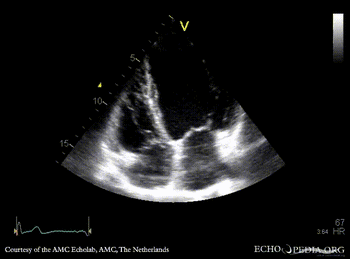

Apical aneurysm of LV

A4CH: dilated left ventricle, apical aneurysm A2CH: apical aneurysm